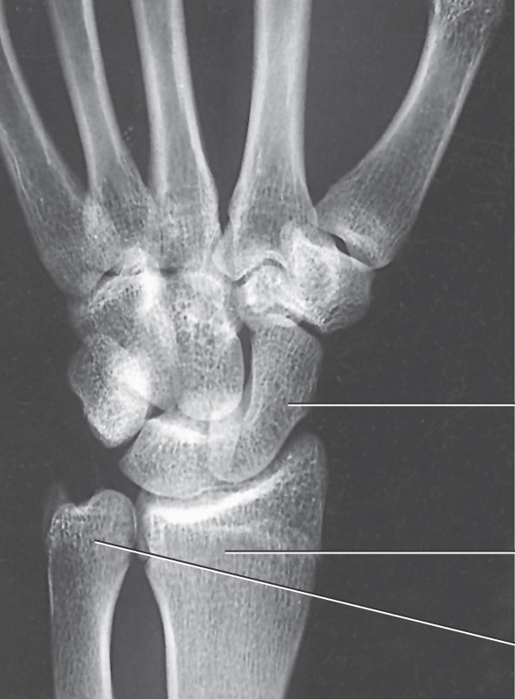

What position is demonstrated?

PA Oblique Wrist